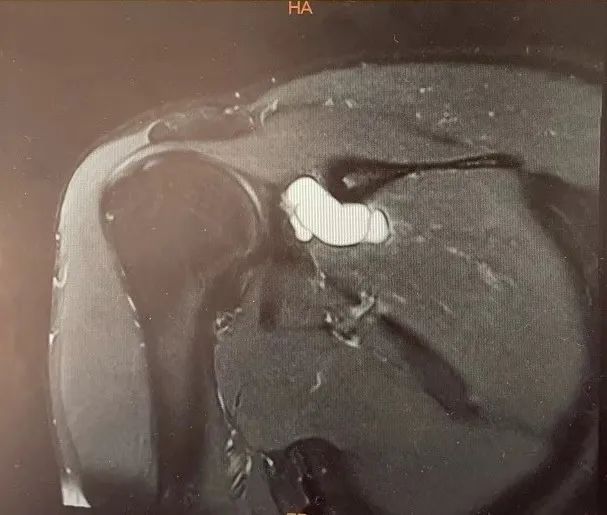

随即,我们安排了右肩关节MRI检查明确病因:右冈盂切迹旁见一个大小约15*35mm分房及分叶囊肿,冈下肌信号增高。

注:蓝色示肩胛上神经,红色圆圈示冈盂切迹囊肿处。

综合以上考虑:右肩冈盂切迹囊肿伴肩胛神经卡压综合征可能大,冈下肌变形水肿。